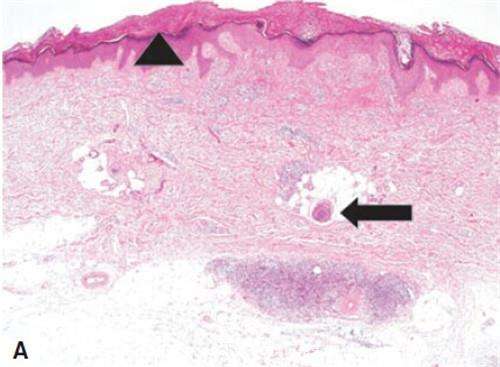

結節(jié)性癢疹是一種慢性炎癥性皮膚病,以劇癢和結節(jié)性損害為特征。病因與昆蟲叮咬,胃腸功能紊亂,內(nèi)分泌代謝障礙及神經(jīng)、精神因素有關。本病女性多見。皮損好發(fā)于四肢,也可見于腰臀部,最多見于小腿伸側(cè)。